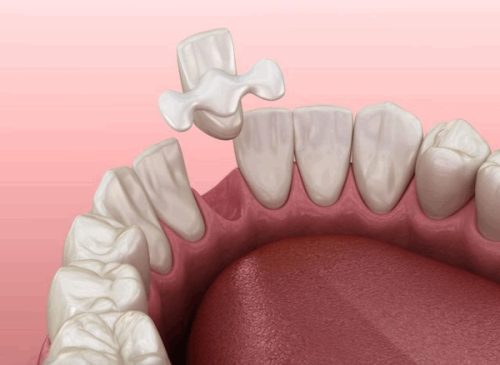

本文围绕“补牙怎么补”介绍了3个关键步骤。补牙前,清理龋坏组织,不同程度龋坏处理方式有别,怕疼可局部麻醉。补牙时,根据牙齿缺损情况选择直接填充、嵌体修复、全冠修复或根管治疗。补牙后,2小时内避免进食,24小时不用患侧嚼硬物,养成良好口腔卫生习惯,定期检查,控制甜食摄入。